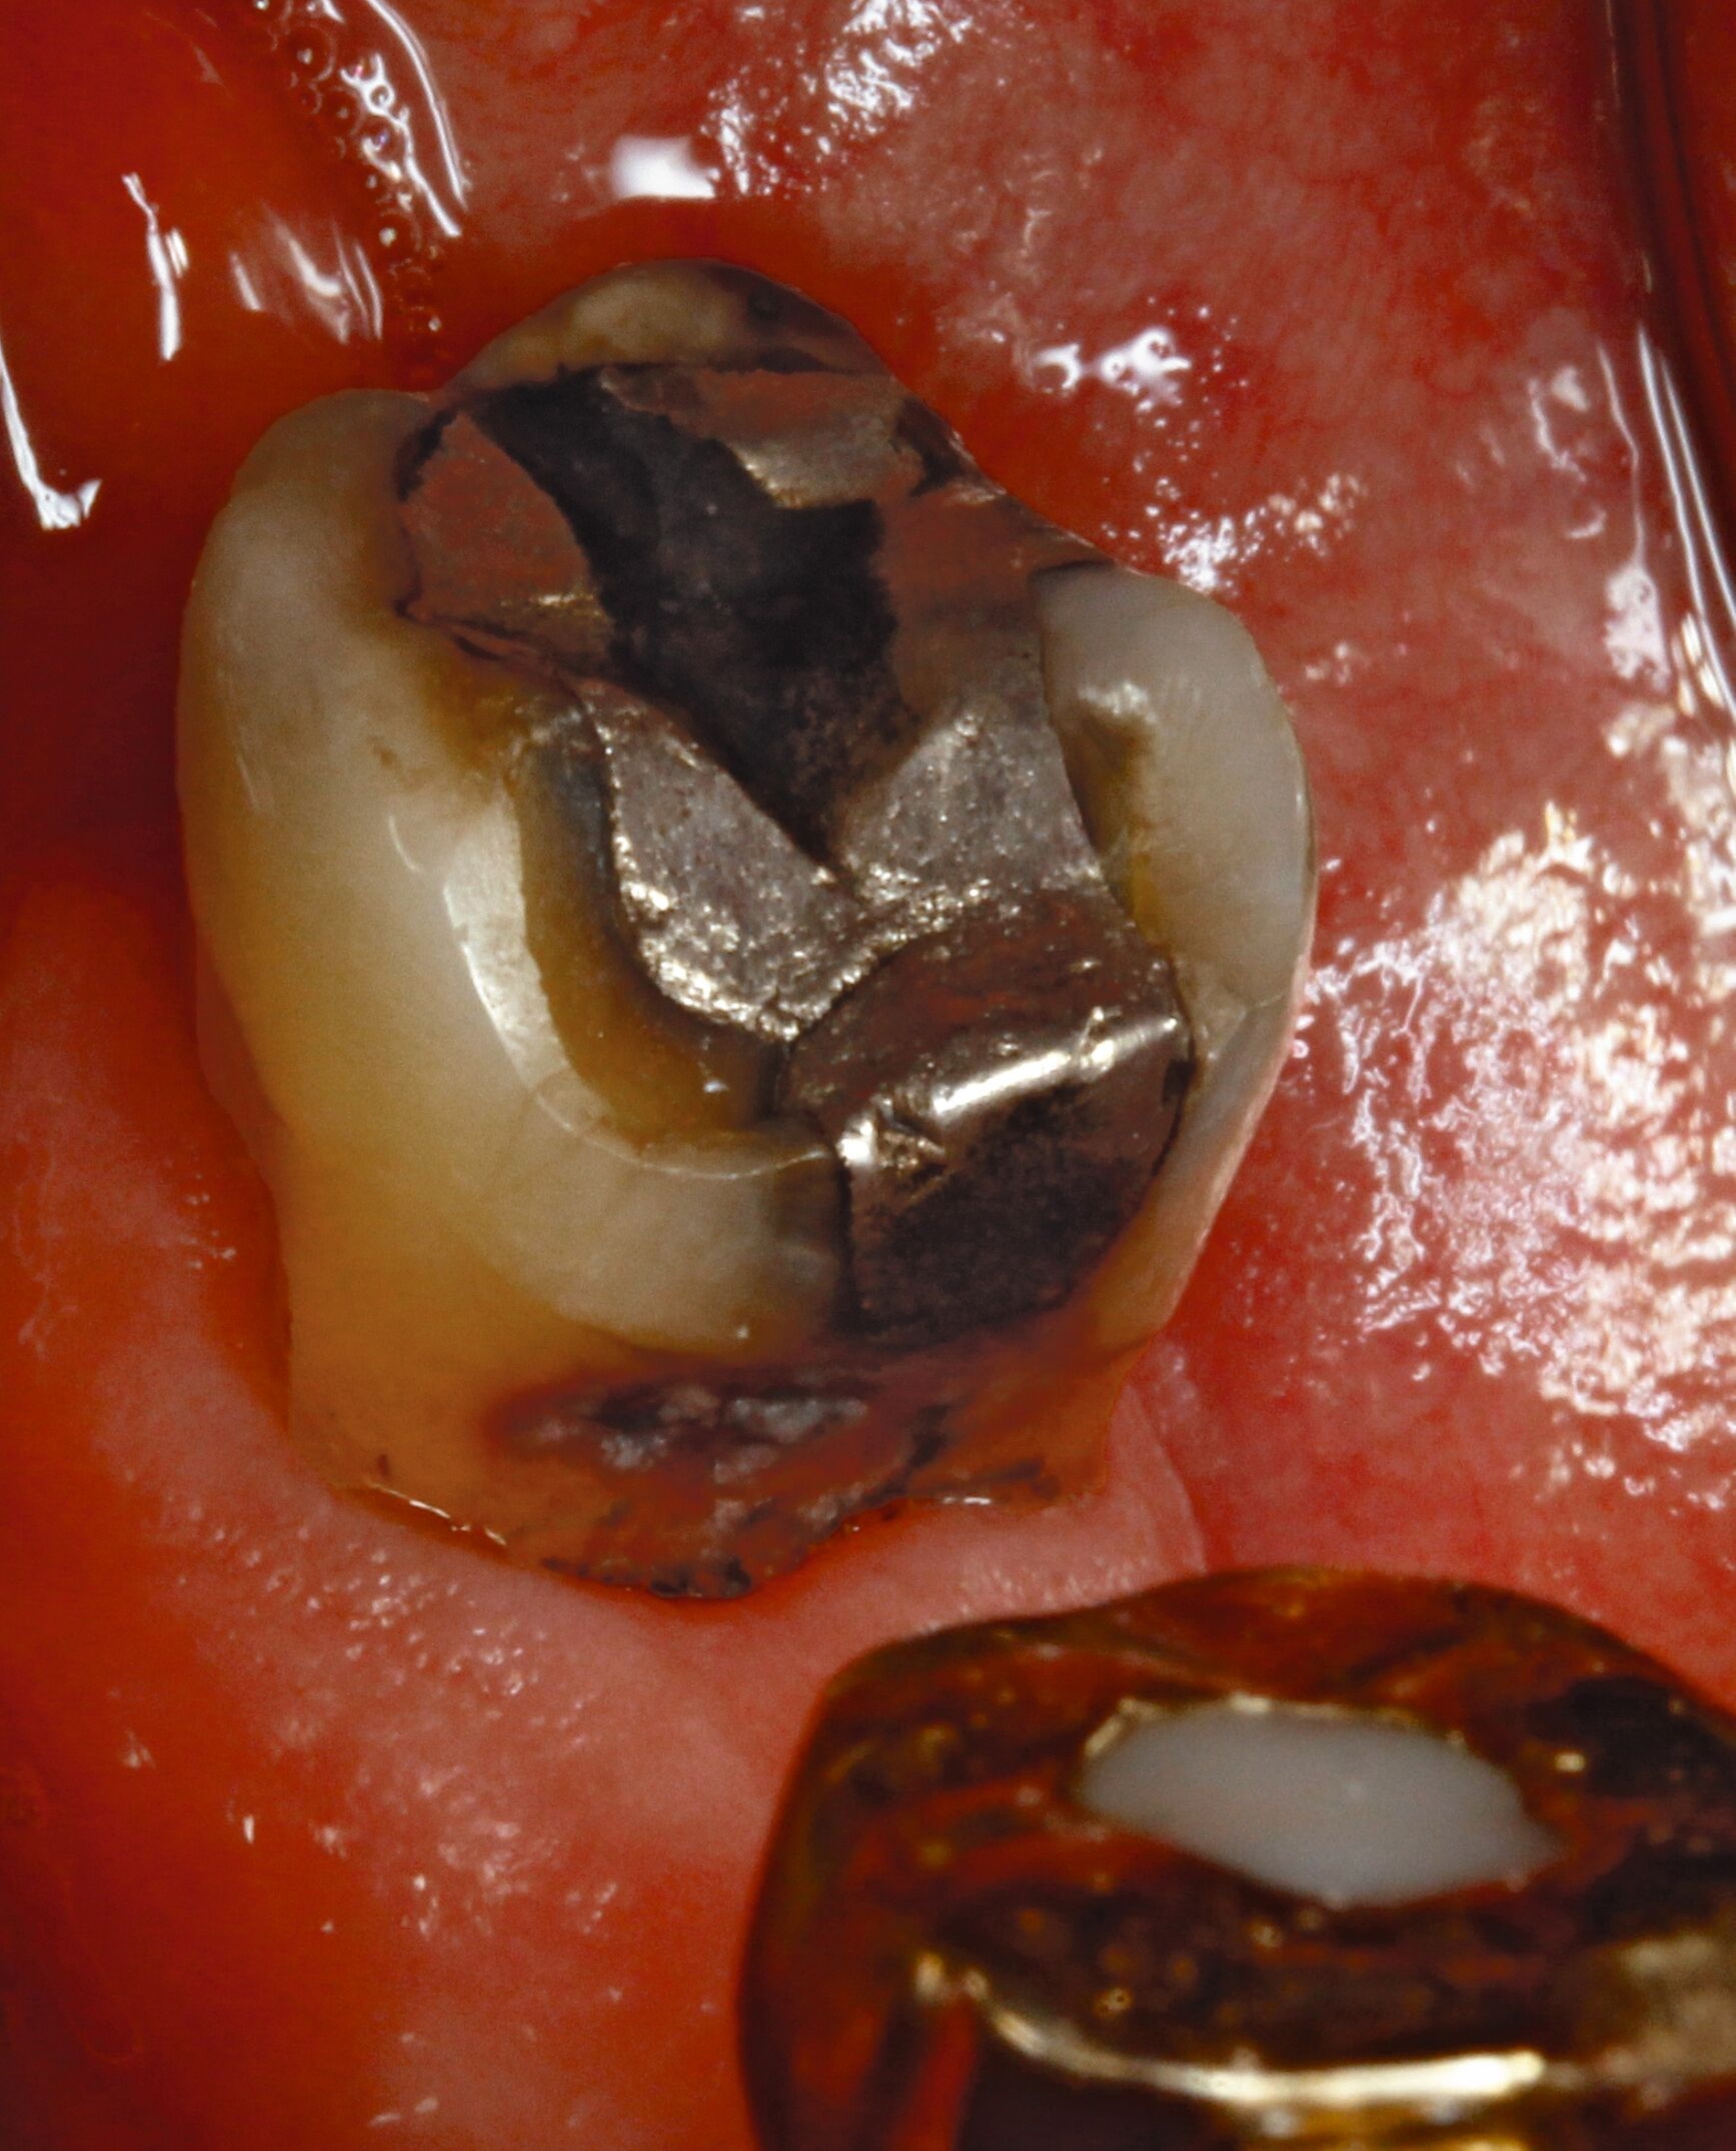

Silberdiamminfluorid ist eine wasserlösliche Verbindung, die aus Silberionen (Ag+), Ammoniak (NH₃) und Fluoridionen (F-) besteht. Ammoniak dient in dieser Verbindung als Stabilisator, indem es die Lösung alkalisch hält. Bei einer Konzentration von 38 Prozent entspricht das einer Konzentration von 44.800 ppm Fluorid und 255.000 ppm Silberionen. In seiner physikalischen Erscheinung ist SDF eine klare bis leicht gelbliche Flüssigkeit mit einem charakteristischen metallischen und leicht ammoniakartigen Geruch. Aufgrund der hohen Alkalität kann es bei Schleimhautkontakt zu leichten Reizungen kommen (Abbildung 2).

Eine bekannte Nebenwirkung bei Anwendung auf kariösen Läsionen ist die Schwarzfärbung des behandelten Bereichs (Abbildungen 3, 4). Verfärbungen können aber auch bei Applikation auf kariesfreien Wurzeloberflächen entstehen, diese sind jedoch mit einer professionellen Zahnreinigung gut zu entfernen (Abbildung 2).

Tatsächlich zeigt die klinische Erfahrung, dass es möglich ist, bei mehrmaliger Applikation innerhalb eines Vierteljahrs auch sehr aktive Läsionen mit taktil weicher Oberfläche trotz eingeschränkter Mundhygiene gut zu erhärten (Abbildung 4). Für die koronale Karies bei Kindern konnte die bessere Wirkung nach wiederholter Anwendung allerdings nicht bestätigt werden. [Smutkeeree et al., 2025].